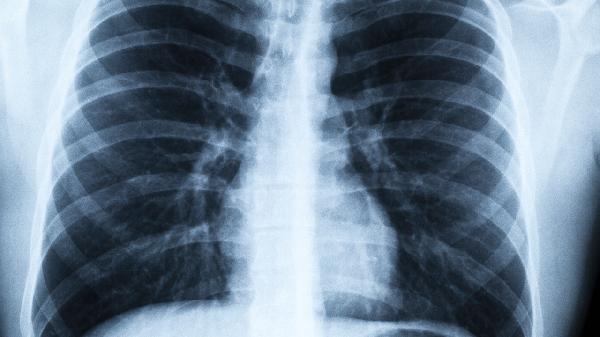

1、每年一次低剂量CT

普通胸片会漏诊40%的早期肺癌,低剂量CT能发现3毫米的微小结节。